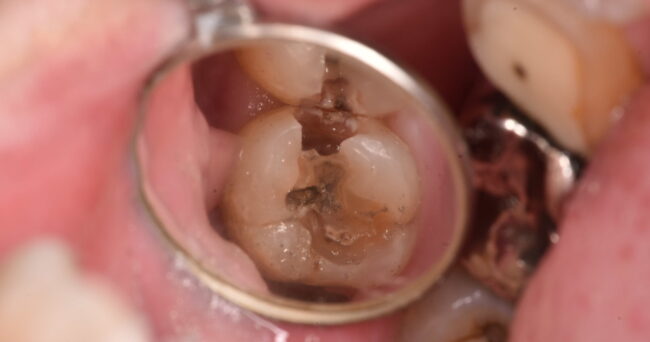

神経の部分をキレイにしました。青いところは、まだ感染が残っているところです。青い部分は基本的に取り除かなければならない部分ですので、やはりこの歯を残すのは、かなり難しい状況です

悪い部分を取り除いて、横から見た状態です。

上から見ると問題なさそうだった部分も、薄くて割れそうなのがわかるでしょうか?ですので、歯として使える部分は、上から見た時よりもさらに少ないのです。位置関係的にも歯として残すメリットが少ないので、やはり第一選択としては抜歯を考えます。